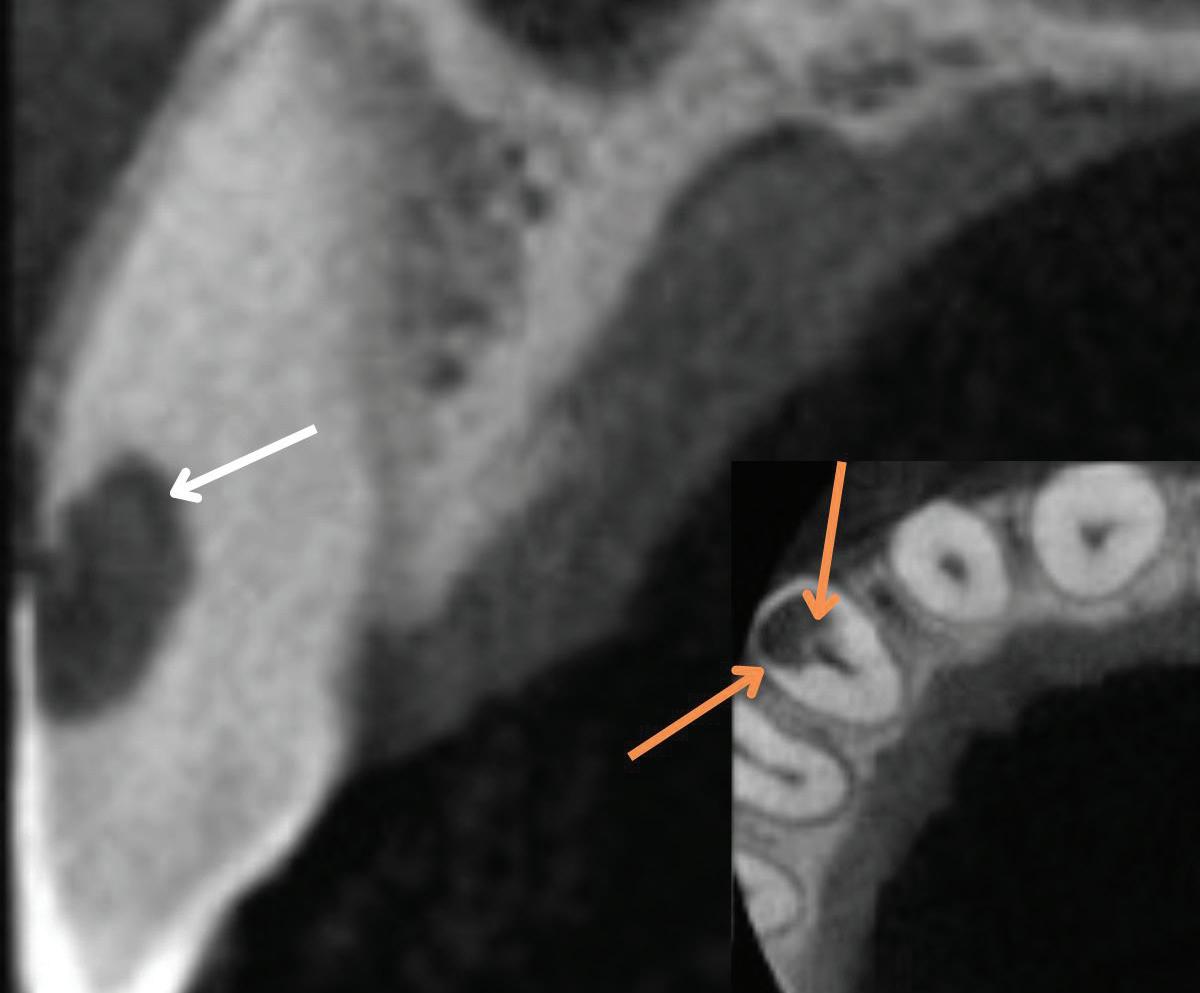

Fig 2. Calcium hydroxide extrusion. During treatment of the mandibular left first molar, dysesthesia (burning pain) and paresthesia resulted from a substantial overfill of calcium hydroxide into the inferior alveolar nerve canal. (Courtesy of

Fig 4. Fenestration involving the maxillary right first molar. A. The periapical radiograph fails to demonstrate the presence of a fenestration at the mesiobuccal root. B. The axial CBCT image clearly depicts the fenestration. C. The coronal CBCT image also reveals the fenestration.

Fig 5. Fenestration involving the maxillary left central incisor. A. The periapical radiograph fails to demonstrate the apex protruding into the sinus. B. The CBCT 3D reconstructed volume clearly demonstrates the fenestration.